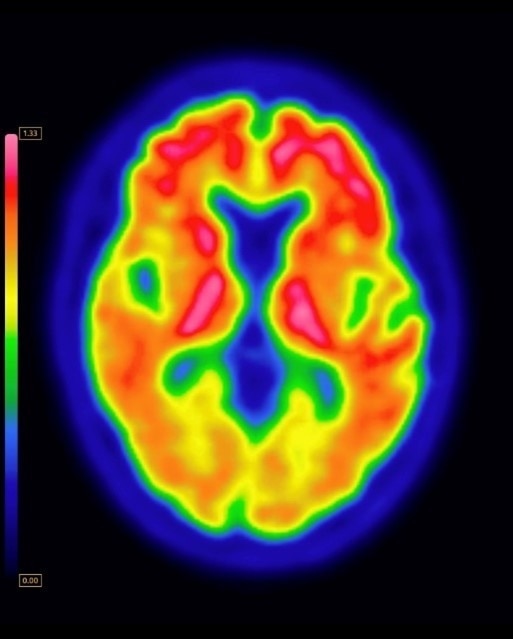

Photonova™ Spectra

GEHC announced the submission of a 510(k) to the U.S. FDA seeking clearance for Photonova™ Spectra.